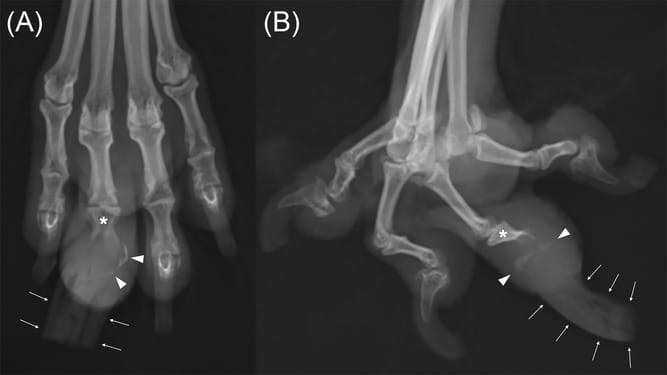

Dorsoplantar (A) and mediolateral (B) radiographs of a dog with keratoacanthoma of the fourth digit (Technique: kVp, 48; mAs, 5.0). Osteolysis is present in both P2 and P3 with well-defined and smooth margins (asterisk). Osteolysis involves 50% of P2, > 90% of the P3 ungual process, and > 90% of the P3 ungual crest (white arrowheads). The nail is enlarged and straightened with cracking (white arrows)